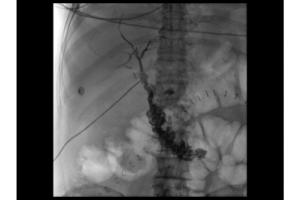

Рентгенография

Семейство рентгенографических систем компании Siemens Healthineers включает в себя широкий спектр продуктов и решений: системы для обычных исследований, травматологии и ортопедии, а также специализированные рабочие станции для исследования грудной полости. Эти системы могут применяться в самых разных областях – от исследования черепа, позвоночника и брюшной полости до исследования конечностей.

Цифровые рентгенографические системы

В цифровых системах применяются детекторы для захвата изображений и проведения диагностики

Обнаружение MAX для более четкого изображения

Большой динамический плоский детектив MAX размером 43 см х 43 см обеспечивает больший охват пациентов как динамическими, так и статическими изображениями. Уникальные функции Siemens CARE, такие как CAREPOSITION(опция), гарантируют, что вы получите правильное изображение при правильной дозировке.

Более точная съемка - с динамическим детектором MAX и SmartView. Динамический плоский детектор MAX размером 43 см x 43 см MAX обеспечивает превосходное покрытие для рентгенографии и рентгеноскопии и обеспечивает изображения с высоким разрешением для большей точности и эффективности.

MAX вашей производительности. 43 × 43 см (17 дюймов × 17 дюймов) плоский детектор обеспечивает высококачественную динамическую и статическую цифровую визуализацию и обеспечивает на 116% больший охват пациентов, чем 33-дюймовый (13 ") усилитель изображения. 783 kHU идеально подходит пациентам с ожирением и более длительными процедурами, что позволяет продолжить исследование и не ждать охлаждения трубки.

Максимальное качество изображения. Динамический детектор MAX обеспечивает более детальную информацию о пациенте, предоставляя изображения без искажений до 3,4 lp / mm - улучшенные уникальным DiamondView Plus для улучшения детализации кости и контраста мягких тканей рентгенографических изображений. При флюороскопии оптимизация цифровой плотности (DDO) максимизирует высококонтрастные изображения, чтобы улучшить контрастность изображения без потери детализации.

Качество изображения MAX. Качество изображения является ключевым для проверки качества и точности. Именно поэтому Luminos dRF Max с обнаружением MAX применяет интеллектуальные инновации на каждом этапе процесса формирования изображения. Это уникальный способ Siemens предоставить комплексную технологию обработки изображений.

Качество изображения MAX

Качество изображения является ключевым для проверки качества и точности. Именно поэтому Luminos dRF Max с обнаружением MAX применяет интеллектуальные инновации на каждом этапе процесса формирования изображения. Это уникальный способ Siemens предоставить комплексную технологию обработки изображений.

DiamondView Plus. DiamondView Plus улучшает контрастность и детализацию изображения, обеспечивая отличное качество снимков для рентгенографии. Он улучшает контрастность костной ткани и мягких тканей, не увеличивая дозу.

Оптимизация цифровой плотности (DDO). DDO обеспечивает согласование высококонтрастных рентгеноскопических изображений, одновременно улучшая контрастность, без потери деталей в очень светлых или темных областях. Это позволяет видеть больше информации на всем изображении, что особенно важно для структур с большими изменениями плотности.

Автоматическое окошко и автоматический затвор. Автоматический затвор повышает контрастность как живых, так и неподвижных изображений с автоматической и динамической регулировкой коллимированной границы до черного - в то время как Auto Window обеспечивает постоянную живую яркость изображения во время движения пациента или системы, даже в более сложных областях, таких как сундук.